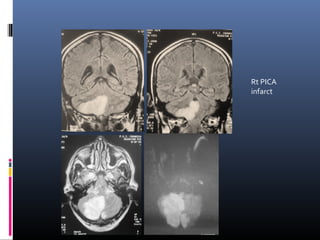

Rt PICA

infarct

SCA infarct